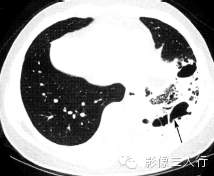

肺隔离症

(图2) |